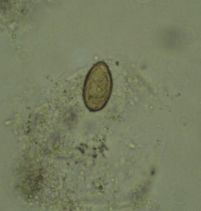

วัดความรู้ว่ารู้จักไข่พยาธิแค่ไหน